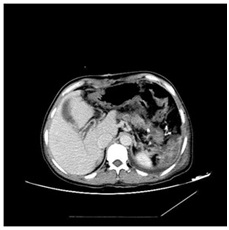

A 51 year old woman suffered from a first episode of fresh blood vomiting and discomfort of abdominal distention after 2 years working on spray paint in a private furniture factory in China mainland. Meanwhile, we don’t find any sign of swollen skin and other complications and she denied the feeling of itch. She repeatedly complained that her health went worse gradually since she began to work on spray paint, when compared to her previous medical health record. Hence, she highly suspected that her symptoms might be associated with her work environment or some paint solvents. She and her family hoped clinicians could confirm or exclude her suspicion during therapeutic course in this admission. Her words arouse our great interest and we decided to decode the conundrum. Amazingly, no specific clues were obtained from her family history, appetites and general laboratory tests. Further enhanced contrast computed tomography of abdomen showed special findings, including isolated gastric varices, major portal vein thrombosis (red arrowhead), focal splenic vein stenosis (blue arrowhead), and splenomegalia complied with focal splenic, but myelofibrosis was confirmed by bone marrow biopsy and the expression of JAK2-V617F was detected in her peripheral blood sample (Figure 1).

Figure 1: Special findings, including isolated gastric varices, major portal vein thrombosis (red arrowhead), focal splenic vein stenosis (blue arrowhead) and splenomegaly complicated with focal splenic.